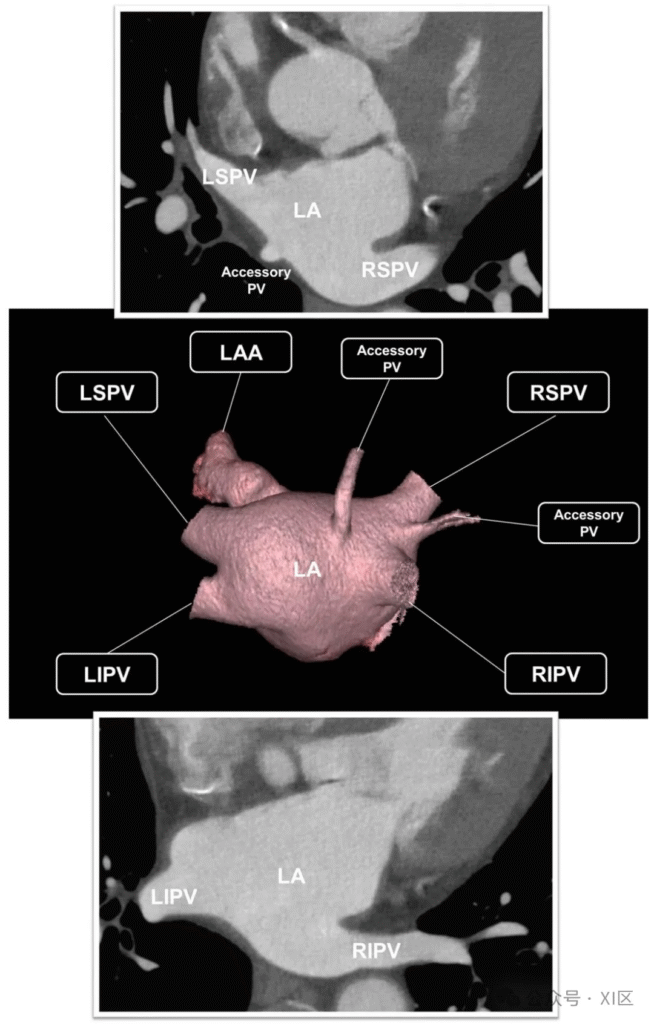

通过心脏计算机断层扫描(CCT)的轴位图像与三维重建技术显示左心房(LA)和肺静脉(PV)的解剖结构。最常见的解剖结构为左心房后部存在四个独立的肺静脉开口:右侧肺静脉中,右上肺静脉(RSPV)与右下肺静脉(RIPV)分别开口,且常被左心房壁分隔;左侧肺静脉中,左上肺静脉(LSPV)与左下肺静脉(LIPV)开口位置通常较为接近,无明显分隔结构。副肺静脉指与同侧上、下肺静脉分开并单独汇入左心房的肺静脉,其命名通常依据所引流的肺段,在人群中的发生率高达 25%,且右侧发生率高于左侧。若存在副肺静脉,其主干通常比主肺静脉更短、管腔更窄,有时可能跨越肺裂 。